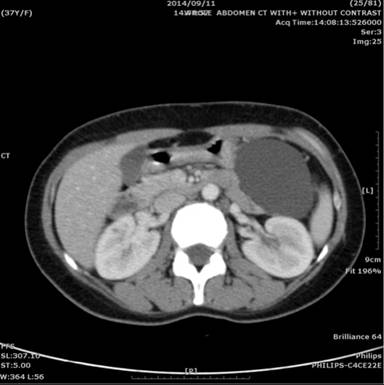

This patient was a thirty-seven-year-old female who complained of intermittent left flank pain and soreness for 2 months. She denied any underlying disease before. A 8x6 cm lobulated cystic lesions with plaque calcification was found at the pancreatic tail incidentally by computer tomography scan of abdomen (Figure 1).

Figure 1. Abdomen CT scan discovered a 8x6 cm lobulated cystic lesions at the pancreatic tail. |